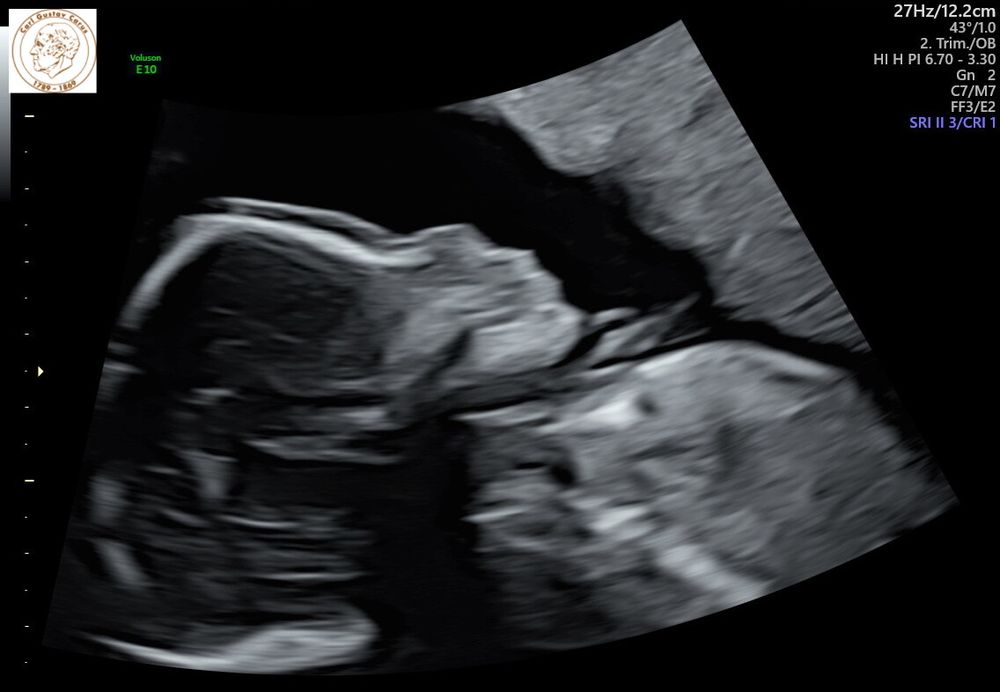

Узи 10 недель.

Девочки, всем привет. Ходила на узи в 10 недель, вроде бы воротниковое пространство расширено или мне кажется?( Переживаю очень сильно..

Таня

это слова врача? плюс генетическое узи (1-й скрининг) делается в строго определенный срок - и не просто так, а потому что только в это время можно определить отклонения по конкретным параметрам. в 10 недель очень сомнительно, что можно что-то рассмотреть…